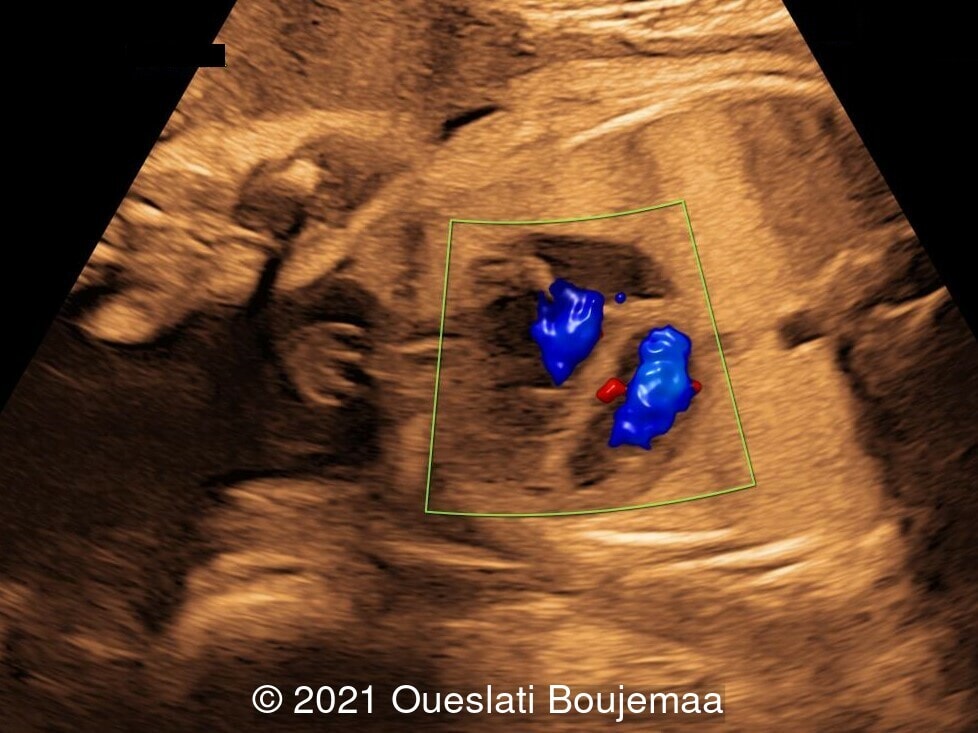

- Cardiac malformation with ventricular septal defect and linear insertion of the atrioventricular valves